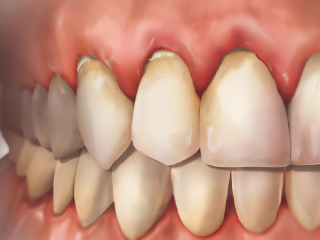

Parodonte Sain

Gingivite

Parodontite Stade III